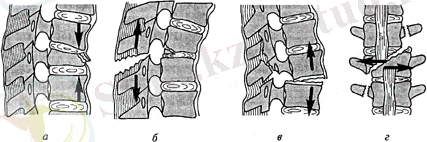

Тұрақты зақымдану бір тірек құрылымын ғана зақымдайды. Оларға денесінің жиекті сынығы, тұйықтаушы пластина сынығы, омыртқа денесінің сына тәрізді компрессиясы жатады. (рис. 3, а, б) .

Тұрақсыз зақымдану екі немесе одан да көп тірек құрылымының зақымдануымен ерекшеленеді. Бұл өте ауыр жарақаттар, осы кезде жұлын мен оның түбіршелерінің зақымдануы және омыртқалардың ығысуы мен басылуы болады. Тұрақсызға сынықтар және сынықты шығулар, омыртқаның сына тәрізді деформациясы, флексионды -ротациялы сынықтар жатады.

«Атылған сынықтар » омыртқаның бүгу, жазу қимылын жасамаған кездегі осьтік жүктемеде пайда болады. Мұндай сынықтар тұрақты және тұрақчсыз да болады. (рис. 3, д) .

Рис. 3. омыртқа сынығы : а - 1/3 денесінің компрессиясы ; б - жиекті, тұрақты) ; в - с компрессия < 1/3 ; г - сынықты шығу (тұрақсыз ) ; д - «атылған ».

УКП AO / ASIF Халықаралық жіктелуі бойынша омыртқа сынықтарын

А типі - омыртқа денесінің компрессиялы сынығы, Втипі - алдыңғы артқы комплекстердің зақымдануы, С типі -ротациялы алдыңғы артқы комплекстердің зақымдануы . Омыртқаның мойын бөлімінің анатомиялық құрылымының ерекшелігіне байланысты өзіндік жіктелуі бар, ал төменгі сегмент зақымдануы тұрақсыз және с типті. рис. 4) .

Рис. 4. УКП бойынша омыртқа сынығының типтері : а - компрессиялы (тип А) ; б - гиперфлексионды (тип В) ; в - гиперэкстензионды (тип В) ; г - ротациялы (тип С) .